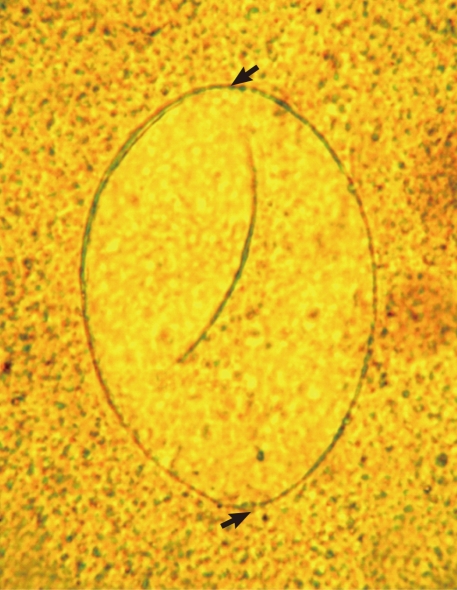

Figs. 3,

4) were 94 µm long (89-99 µm) and 55 µm wide (52-58 µm) (n=10), and had a relatively wide, somewhat inconspicuous operculum, a thin and refractile shell, and abopercular wrinkles terminally. In Kato Katz fecal smears, the operculum and abopercular wrinkles of the eggs are less apparently seen (

Fig. 4).

Fig. 4Another E. ilocanum egg (102×58 µm) found in a Kato-Katz fecal smear of a patient. Note the thin and inconspicuous operculum (arrow; up) and a tiny abopercular knob at its terminal end (arrow; down). ×400.